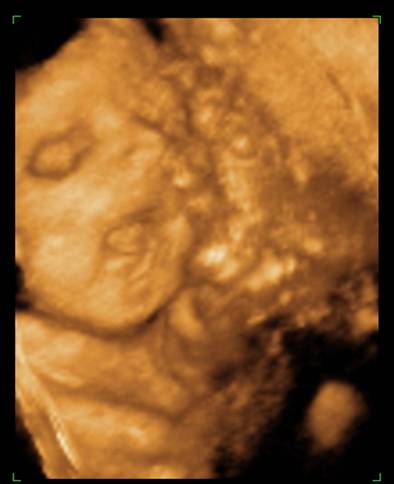

Voltunk 4D-n, rakok fel képeket mindjárt. (apja oda sem nézett, amikor mutatták az arcocskáját, csak nyavajgott, hogy mikor van már vége, érdemes volt elvinni...) De egyre kisebbnek mérik ezt a babát, és kezdek aggódni. Inkább 29 hetes méretei vannak, mint 30... És a súlya még mindig csak 1366, közben itt már mindenkinek minimum másfél kiló fölötti... :cry:

na, még ezeket megmutatom a kis pöttömről:

Kép

Boruska Fel a fejjel! Aludj egy jót! Embered biztos csak nyűgös volt, majd holnap biztos örömmel nézegeti édes kismanótokat a képeken. És miként sok okos már írta, a méretek csak átlagok, s ezek ugye a nagyobbakból és a kisebbekből tevődnek össze. Könnyebb megszülni egy 3 kg-os babát, mint egy 4,5 kg-t :) . És 1 hetes méret eltérés igazán semmitmondó. Valamint a súlybecslés az egyik legbizonytalanabb tényező, szóval ezen tényleg ne aggódj! Az utolsó képen én úgy látom mosolyog Berci. Álmodj ezzel a kis mosollyal!